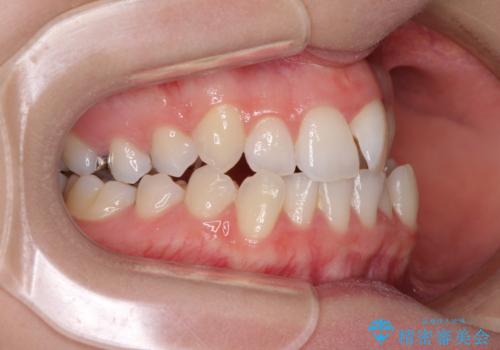

上顎骨の横幅が狭く、奥歯は上顎よりも下顎が外側にある咬合状態でした。

歯列矯正では基本的に骨格を改善することはできませんが、急速拡大装置(MARPE)を使用することで上顎骨を側方に拡大させることができ、咬合状態を大きく改善することができます。

急速拡大装置により骨格はある程度改善されましたが、奥歯の咬み合わせ改善に非常に時間がかかってしまいました。

デコボコを改善させるだけでなく、しっかりとした咬合状態を獲得することができ、患者様には大変満足していただけました。